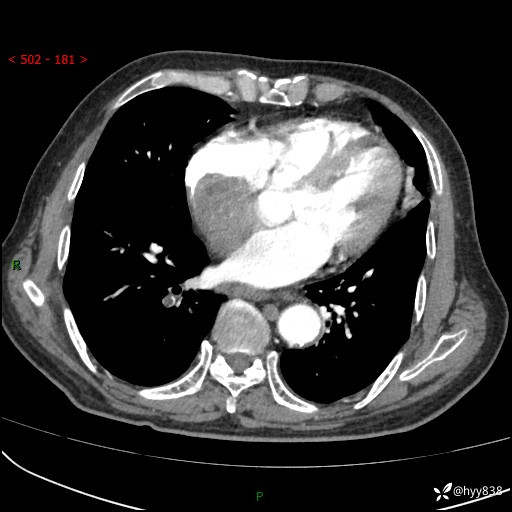

主诉:检查发现心脏肿物1周余。

现病史:患者一周余前因腹胀就诊我院消化科门诊,查心脏彩超提示右房内异常回声(粘液瘤?),无明显心慌、气喘、胸闷,无明显胸痛、咳嗽咳痰等不适,活动量增加后出现心慌、气喘不适。现为求进一步治疗,就诊我科,门诊遂以“心脏肿物”收入院。 自发病以来,精神睡眠一般,食欲尚可,大小便正常,体力下降,体重无明显变化。

胸部CT平扫+增强